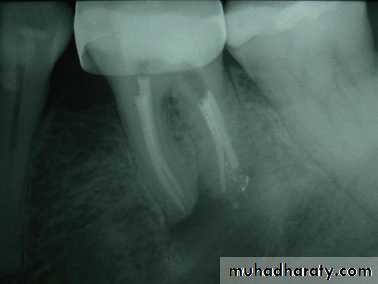

Periapical lesion associated with endodotically treated canals

Regression of the lesion 6 months after retreatment of the tooth